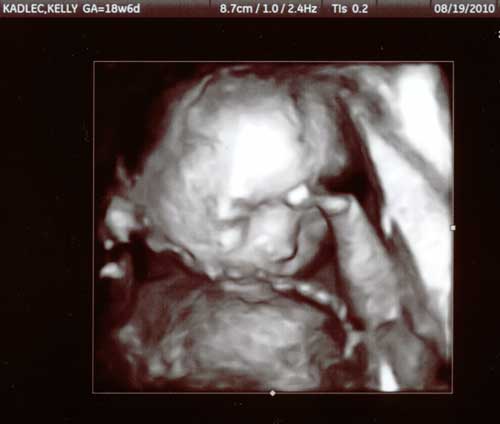

19 August 2010

At our 19 week ultrasound appointment,

the ultrasound tech turned on the 3D feature

to show us some images of his face.

hand

he looks a little camera shy with his hand in front of his face

cord